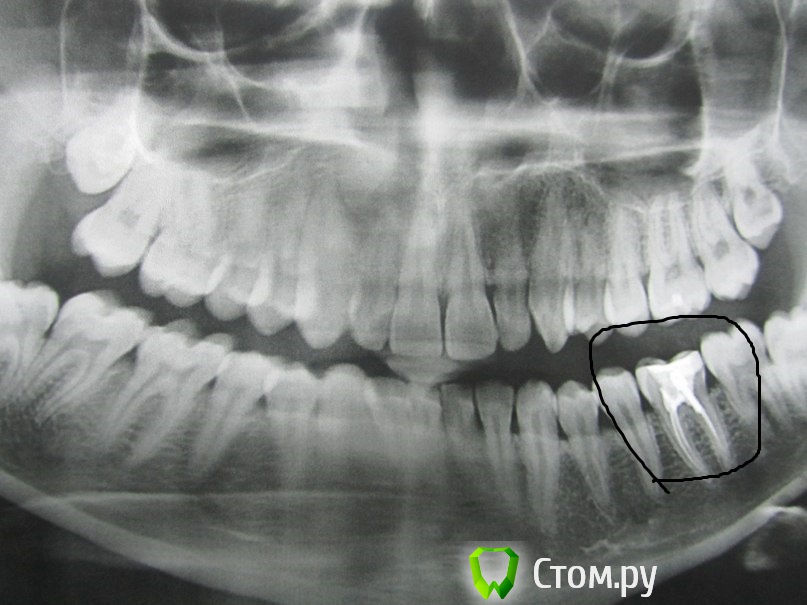

lainux Опубликовано 29 ноября, 2014 Поделиться Опубликовано 29 ноября, 2014 (изменено) Уважаемые врачи, добрый вечер. Два месяца назад установили штифт, зуб периодически стал беспокоит, чувствуется при постукивании по нему небольшая боль. Пошёл к врачу которая делала со снимком, платный кабинет, переделывать отказалась, что её ошибки нет и каналы запломбированы хорошо, сказала попить антибиотики, что продлит неудаление зуба, расстроился нереально. По пути проконсультировался в другой стоматологии, сказали что не долечен канал со штифтом который и надо переделывать, но никак не удалять. Прошу помочь и проконсультировать как быть Изменено 29 ноября, 2014 пользователем lainux Ссылка на комментарий